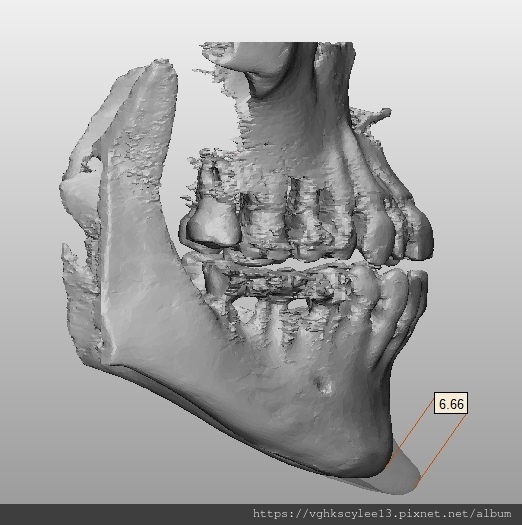

(下圖)3D模擬後工程師版的設計下巴假體的外型。

經過李醫師醫師對客戶外型的判斷,修改工程師的設計,建議更改後的假體模型(下圖)

(上圖)經過李醫師醫師對客戶外型的判斷,修改工程師的設計,建議更改後的假體模型。所以嘍,醫師的美感與專業度必須要做判斷,3D列印只是精準工具但是必須有專業醫師的判斷才可以完美!

下圖: 在李醫師確認後完美精準例印

窄小後縮的下巴,以精準3D列印技術來客製化醫師判斷後的外型下巴假體,一起改善嘴形相對的狀態。

窄小後縮的下巴,以精準3D列印技術來客製化醫師判斷後的外型下巴假體,一起改善嘴形相對的狀態。

3D模擬後 列印出吻合的設計下巴假體

(下圖範例:極後縮下巴整形)3D列印客製化複合型骨水泥下巴假體:3D影像評估,經導航客製化假體矯正後縮。

骨架明顯後縮不足